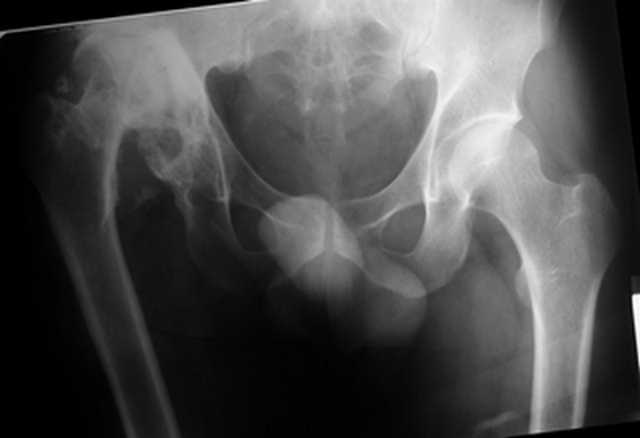

Уважаемые коллеги. Пациент 30 лет 3 года назад в результате травмы получил травматический дефект нижних конечностей до в/3 голеней, был пропущен вывих бедра.

В настоящее время очень неплохо ходит на протезах, движения в неоартрозе близки по объему к здоровой стороне. Основная жалоба - выраженная боль при ходьбе. планируем двухэтапное эндопротезирование - задним доступом мобилизовать проксимальный отдел бедра, резецировать шейку, аппаратом низвести бедро(головку оставить там где она есть, так как больших дефектов не видно(может пригодится в последующем?)). Вторым этапом бесцементное эндопротезирование. Насколько такой вариант реалистичен? Доступ для второго этапа? Может быть другие варианты?С уважением, Максим

Низводить надо обязательно, лучше в аппарате и лучше без остеотомии.

Если в аппарате низводиться не будет, то из небольшого доступа, лучше под контролем С-дуги выполнить остеотомию шейки. Без предварительного

низведения максимально возможная коррекция длины - 2,5-3 см.

Решение по ВВ придется принимать по месту.... Сумеете "подрыться" и получить хорошее покрытие чашки (+2 винта об-но) - хорошо, если нет -

костная аутопластика из головки.

Если есть необходимость, представлю Р-граммы разных вариантов